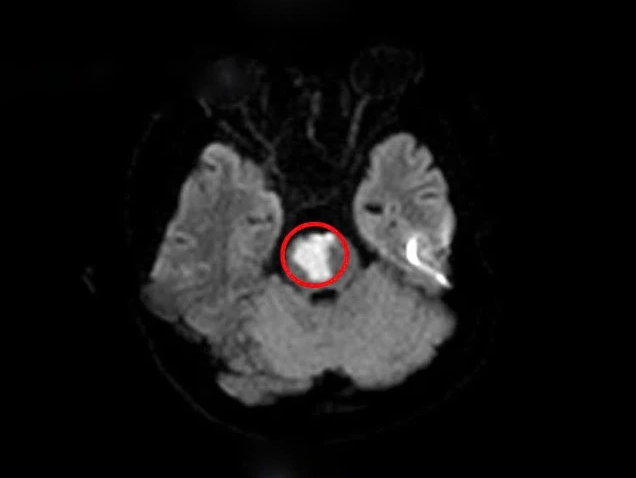

Sau khi tiến hành chụp MRI sọ não, kết quả cho thấy người bệnh có khối nhồi máu tiểu não, cầu não do tắc động mạch thân nền. Trên kết quả xét nghiệm máu có rối loạn lipid máu, một yếu tố nguy cơ dẫn đến các vấn đề tim mạch và mạch máu não.

Tổn thương nhồi máu vùng tiểu não của người bệnh (vùng khoanh tròn màu đỏ) - Ảnh: BVCC

Ngoài ra, khi làm các xét nghiệm chuyên sâu, người bệnh được phát hiện bất thường trong hệ gen gây tăng nguy cơ tạo huyết khối tắc mạch.